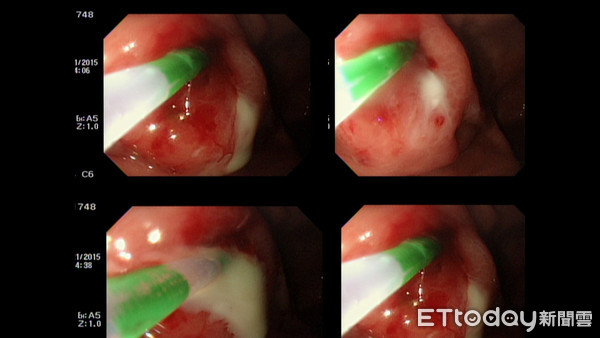

▲患者胃鏡可明顯看到白膿自潰瘍流出。(圖/義大醫院提供)

義大癌治療醫院胃腸肝膽科醫師曾兆明指出,患者本身有糖尿病病史,但無定期追蹤控制,且平常會赤腳在水池邊的草地散步。這次就診,除了有慢性腹痛,伴隨輕微發燒的症狀外,腹部電腦斷層顯示,脾臟及胃體部都有潰瘍,並確診為類鼻疽感染,其常見的病徵包括發燒、頭痛、局部痛楚或腫脹、潰瘍、胸痛、咳嗽、咳血及局部淋巴結腫大。